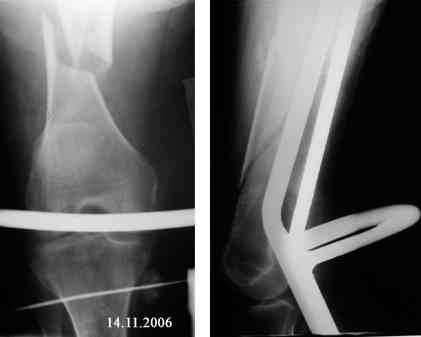

Представляю вашему вниманию снимки в динамике